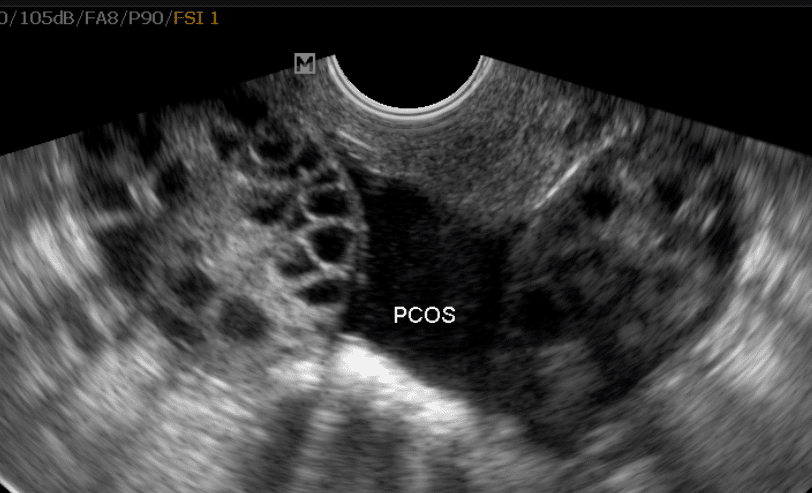

در نتیجه، افرادی که سندرم تخمدان پلیکیستیک دارند، معمولاً چرخههای قاعدگی نامنظم، پریودهای از دست رفته و تخمکگذاری غیرقابل پیشبینی را تجربه میکنند. ممکن است کیستهای کوچک فولیکولی (کیسههای پر از مایع که حاوی تخمکهای نابالغ هستند) بر روی تخمدانها در سونوگرافی مشاهده شود که ناشی از عدم تخمکگذاری (آانوولاسیون) است. با این حال، با وجود نام «پلیکیستیک»، وجود کیست بر روی تخمدانها الزامی نیست و کیستها معمولاً خطرناک یا دردناک نیستند.

کیستها: بسیاری از افراد مبتلا به PCOS تخمدانهایی بزرگتر یا دارای فولیکولهای متعدد (کیسههای تخمک) در سونوگرافی دارند.

در بیشتر موارد، پزشک شما میتواند پس از معاینه و بررسی علائم، سندرم تخمدان پلیکیستیک را تشخیص دهد. ممکن است برای تأیید تشخیص، آزمایش خون یا سونوگرافی انجام شود.

انجام سونوگرافی لگن برای بررسی تخمدانها، ضخامت پوشش رحم و سایر علل خونریزیهای غیرطبیعی

تخمدانهای بزرگشده یا ظاهر پلیکیستیک تخمدانها در سونوگرافی: بسیاری از افراد دچار کیست نمیشوند.